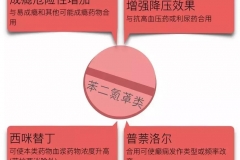

健康科普:6問催眠藥-會產(chǎn)生依賴嗎?哪些人不能吃?

健康科普:6問催眠藥-會產(chǎn)生依賴嗎?哪些人不能吃?

科普中國-樂享健康作者:李潔璇 長春市第六醫(yī)院 副主任藥師